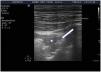

Air does not conduct ultrasoundTherefore, if the lung is ventilated below the pleural line, we will only see artifacts. If otherwise, we observe the true anatomical image, as in pneumonic consolidation or effusion with lung collapse (Suppl. Fig. 1).5

All the signs/artifacts arise from the pleural lineOn interpreting the image, we first should identify the pleural line, which is seen as a hyperechoic structure located between the two acoustic shadows generated by two consecutive ribs. By positioning the probe perpendicular to the ribs we obtain the so-called “bat sign” (Fig. 2), and sliding between the visceral and parietal pleura in turn gives rise to the pleural “sliding” sign (Video 1).5,6